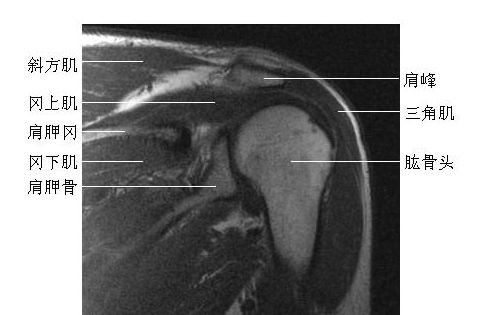

肩关节冠状-MRI图